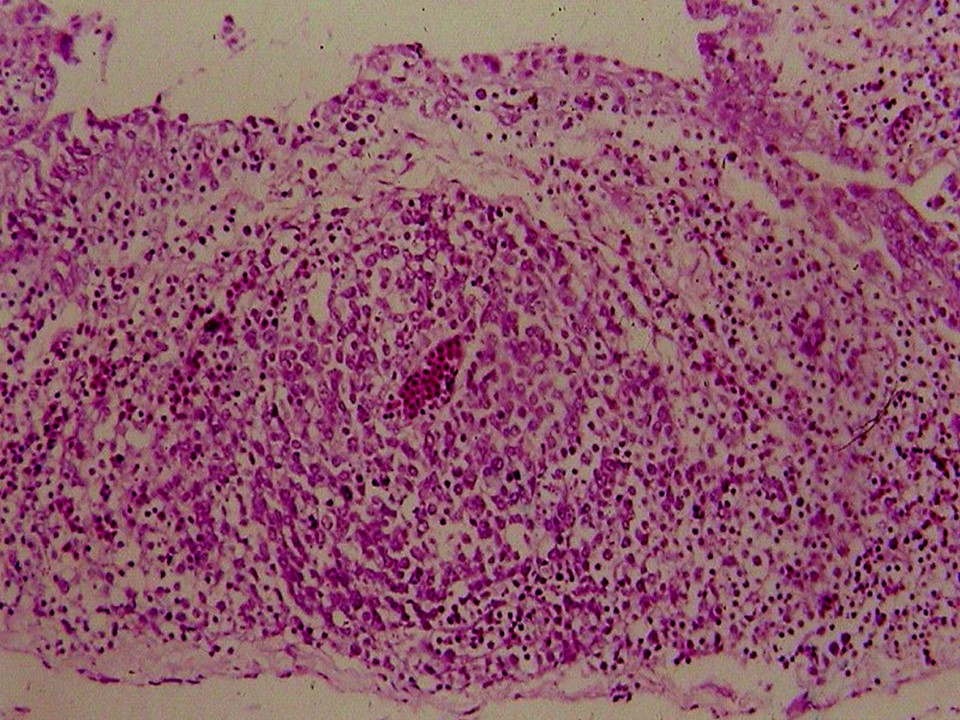

疾病中文名稱:馬立克病

疾病英文名稱:Marek's disease

影像說明:翼神經受侵犯而翅膀下垂,坐骨神經受侵犯呈劈腿狀